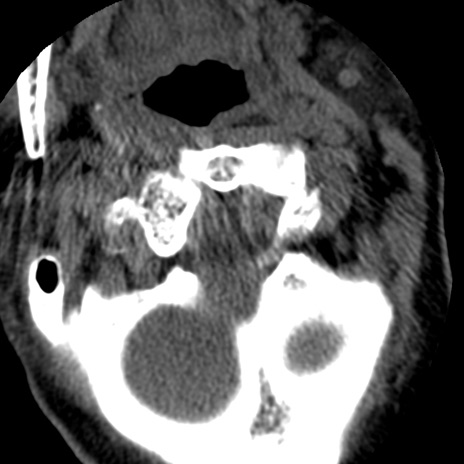

症例50 頚椎CT(横断像)

冠状断像